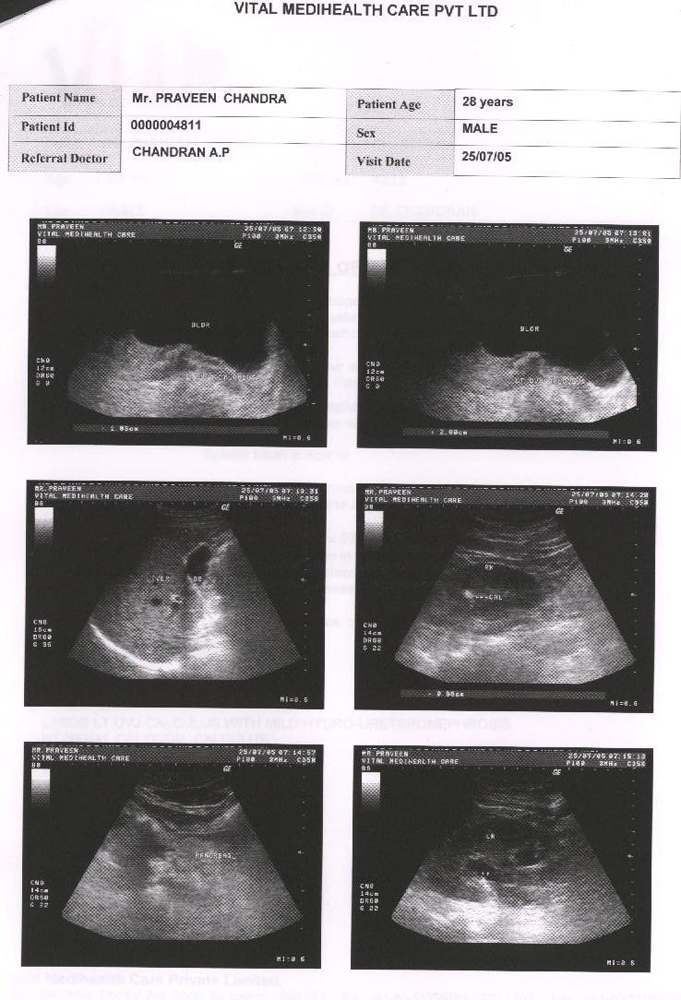

Condition of patient in after 25 days of taking Homoeopathic remedy